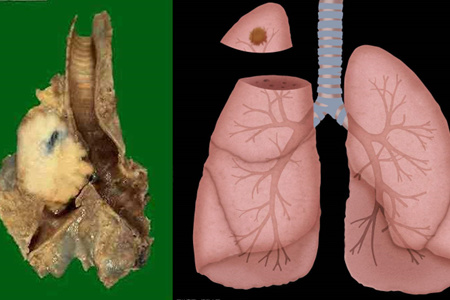

癌症我们应该不陌生,因为现在在我们身边,经常会听到某某某因为癌症而离世。在中国,恶性癌症可以说是致死率非常高的疾病之一。支气管肺癌大家应该或多或少有所耳闻吧,这个疾病主要是支气管和肺部因为受到外界的污染和刺激,导致肺部和支气管发生恶性肿瘤,到目前数据显示,该疾病是致死率最高的恶性肿瘤之一。

支气管肺癌的症状其实非常明显,如果是在癌症的早期,主要表现为咳嗽,痰中有血,有的患者会有气短等等症状,这个时候患者就需要到医院做一个胸外科检查,及时发现疾病。而到了中后期之后,患者的症状会明显加强,比如说咳嗽得更加剧烈,甚至会有呕血的现象,而且胸部会出现疼痛,气短也会更加严重,甚至爬一个小小的楼梯都会气喘吁吁。